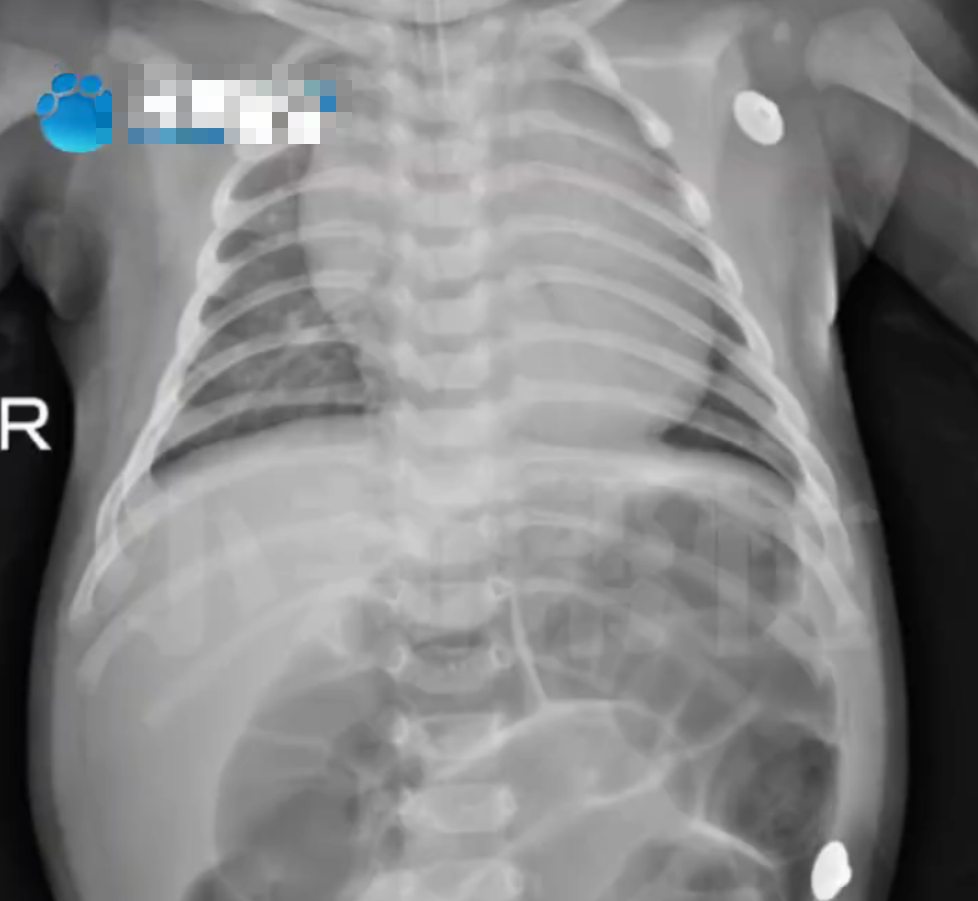

Em bé 52 ngày tuổi ngộ độc Botulinum nguy kịch vì loại nước chữa ho, bổ phổi rất quen từ bà ngoại- Ảnh 1.

Em bé 52 ngày tuổi nhập viện trong tình trạng bụng phình to, suy hô hấp vì ngộ độc Botulinum